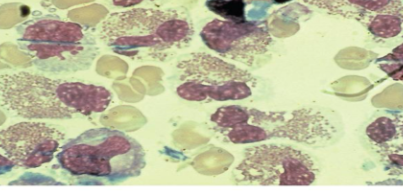

BM contamination

fecal fat stained with Sudan Black III